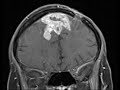

Intracranial Aspergillosis

These images show a large multilobulated, enhancing, markedly T2 hypointense mass centered at the anterior falx cerebri with extension in the parasagittal bilateral frontal lobes with extensive surrounding T2 FLAIR hyperintensity compatible with vasogenic edema. The mass contains several areas of peripheral enhancement and central restricted diffusion which are compatible with abscesses. There is evidence of invasion into the superior sagittal sinus. Given the marked T2 hypointensity of the mass-like components invasive fungal abscesses lead the differential. Pathology confirmed this finding and showed aspergillus.